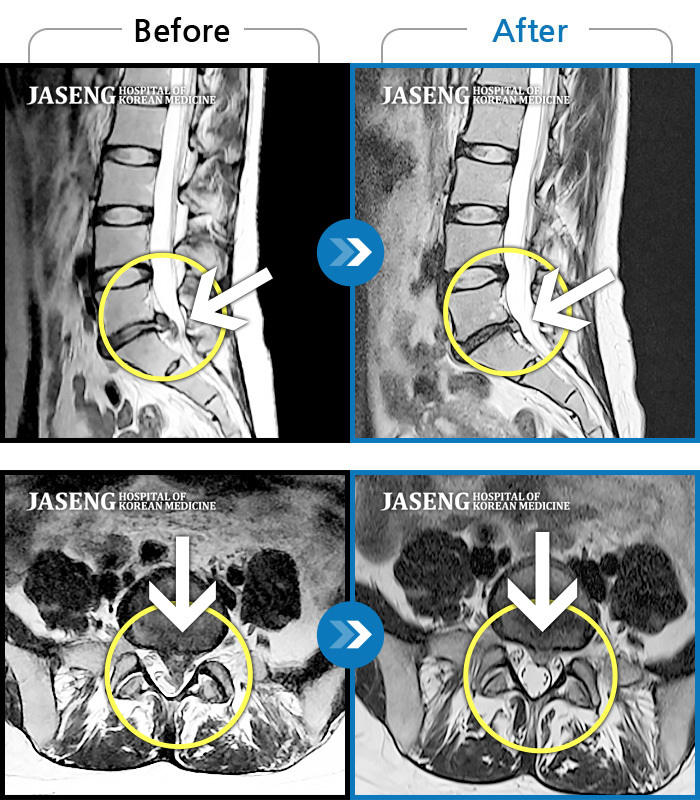

허리디스크

광주 · 김동은 원장

허리 통증과 양측 둔부부터 허벅지, 발목 부위 저리는 증상으로 내원하셨습니다.

촬영시기

2025.05.09 ~ 2025.12.18

2025.12.22